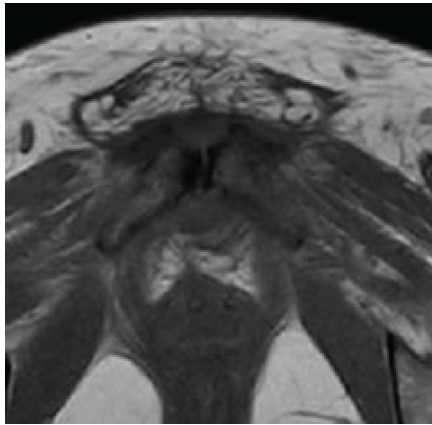

A 42-year-old South Asian woman with a history of hypothyroidism and recurrent UTIs presented with a 2-week history of lower abdominal pain radiating to both lower limbs, associated with high-grade intermittent fever. The pain was spontaneous in onset, progressive, and unrelated to trauma. She had previously received multiple short courses of antibiotics for recurrent UTIs. She presented to our center 10 days after the onset of symptoms. On evaluation, she was febrile (temperature 102°F), with suprapubic tenderness and restriction of active and passive hip movements bilaterally. Initial laboratory investigations revealed neutrophilic leukocytosis (total leukocyte count: 15,000/µL; neutrophils: 13,600/µL) and elevated C-reactive protein (195 mg/L). Urine routine examination demonstrated numerous red blood cells but no pyuria. A contrast-enhanced computed tomography renal stone survey showed perinephric stranding in the retropubic space suggestive of cystitis, with no evidence of collections, hematoma, or pelvic bone fractures. She was empirically started on intravenous piperacillin-tazobactam for presumed acute cystitis, given her history of recurrent UTIs. However, urine culture showed no growth after 48 h, while blood cultures grew MRSA. Antibiotics were escalated to intravenous teicoplanin (400 mg twice daily). Despite 48 h of appropriate therapy, she continued to have high-grade fever and worsening excruciating suprapubic pain radiating to the groin and medial thighs, severely limiting her mobility. Magnetic resonance imaging (MRI) of the pelvis with contrast revealed osteomyelitis of the bilateral pubic bones and superior pubic rami, with abscesses (10 mL and 1.5 mL) around the pubic symphysis, fluid collections in the right adductor and obturator externus muscles, and edema of the obturator internus, externus, and pectineus muscles (Figs. 1, 2, 3, 4).

Figure 1: Axial T2-weighted magnetic resonance imaging of the pelvis showing marrow edema and signal alteration involving the bilateral pubic bones and superior pubic rami, consistent with osteomyelitis.

Figure 4: Axial T1-weighted magnetic resonance image of the pelvis showing altered marrow signal intensity involving the bilateral pubic bones and superior pubic rami, consistent with osteomyelitis. The pubic symphysis appears widened with adjacent soft-tissue edema and early abscess formation. Surrounding muscular edema is noted in the adductor and obturator groups.